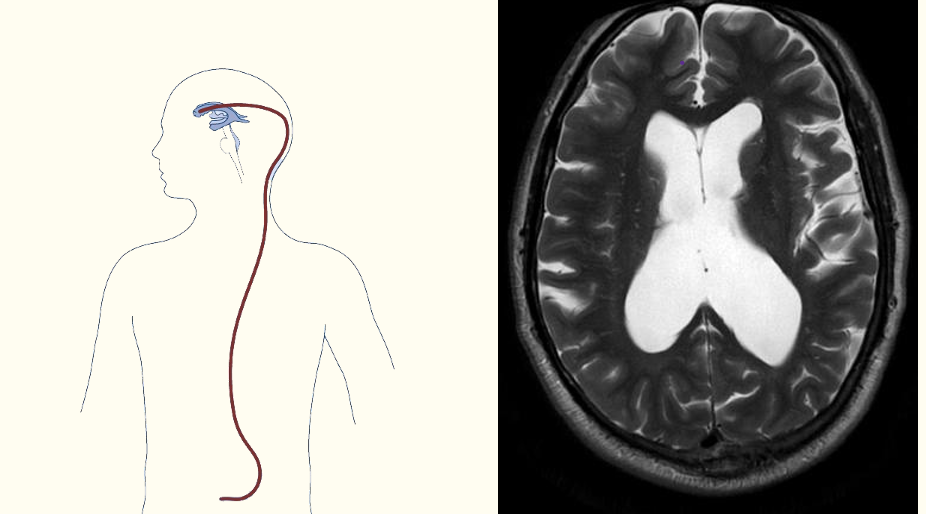

iv) what is the mainstay of treatment? does this fix the cause?

i) primary cause is blockage within the ventricular system

due to tumour, cysts, stenosis (narrowing of ceb aqueduct)

ii) leads to CSF not being able to circulate over the surface of the brain

iii) CSF cant exit the ventricular system therefore ventricles become dilated

iv) treatment = insert a shunt between lateral ventricle to abdo cavity to reduce ICP

- this doesnt fix the cause

HYDROCEPHALUS

i) what type of hydrocephalus is being represented by the pictures?

ii) is the MRI T1 or T2 weighted?

iii) explain the treatment shown

i) non communicating hydrocephalus

ii) T2 weighted as fluid is white

iii) shunt from lateral ventricle to abdomen to decrease ICP